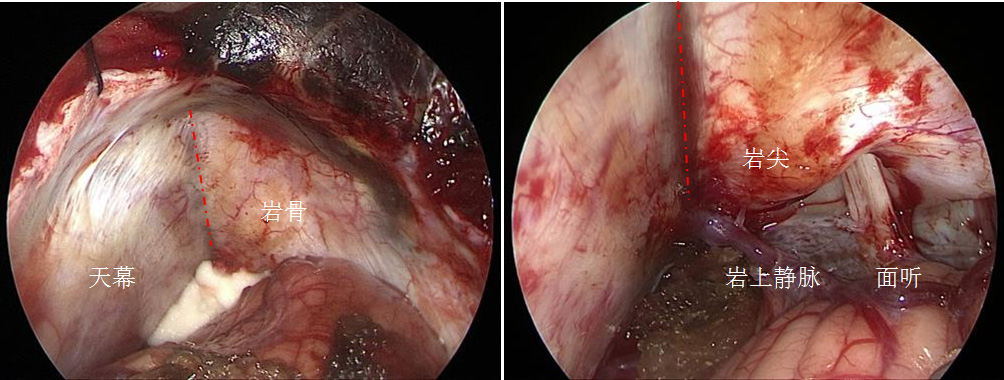

手术开颅和乙状窦后入路一样,头稍偏向对侧满足直上直下的要求,无需剃头,耳后5-6公分直切口,骨瓣到达横窦下缘,脑膜瓣状剪开,从枕大池释放脑脊液,头高脚低位。利用重力及借助脑压板,必要时可扩大骨窗移位横窦或者切除部分天幕来使该入路达到需要的暴露空间。下附一张经此入路手术的通道图片一张(图2)。

图2